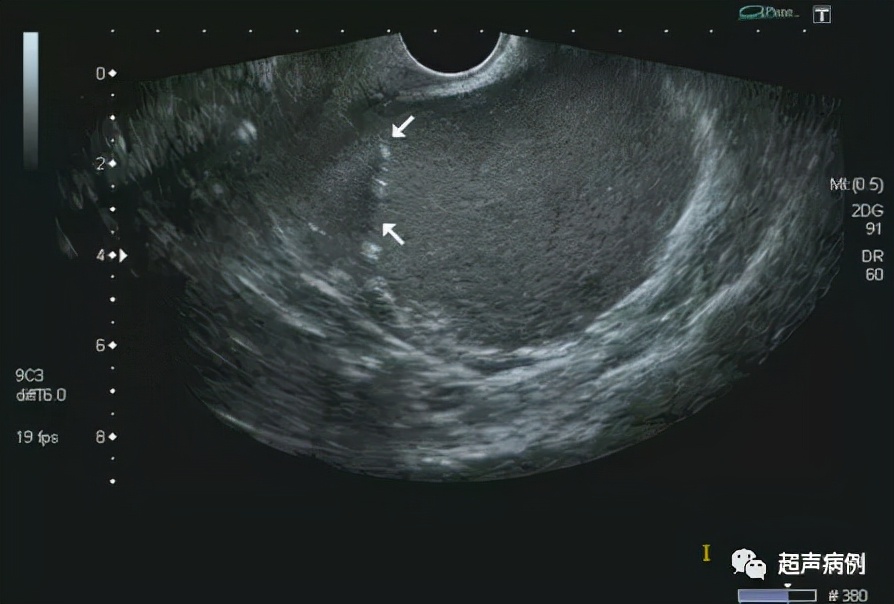

在子宫后方盆腔内查见一约10.4x9.7x7.3cm无回声区

形态规则,边界清楚,内透声差,呈毛玻璃样改变

内可见强回声分隔

CDFI:该无回声区内部及周边未见明显血流信号。